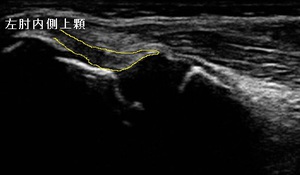

右肘内側 超音波長軸像 左同部正常(健)側

坂戸市小学5年生男児、 少年野球クラブピッチャー。 肘の痛み、右肘内側上顆裂離骨折。

右肘の内側上顆に圧痛、熱感、屈曲時痛、外転外旋(投球動作)時痛が著明でした。超音波観察において、

内側側副靭帯付着部(左右上画像黄色の囲み)の内側上顆前下部に、骨が裂離(剥離)している様子が

認められました(左上画像の丸内矢印)。肘外側には損傷はありませんでした。

小学生の内側野球肘は約4割に起こると言われ、特に小児の場合は成長期であるため、靭帯付着部が軟骨で

剥がれやすい特徴があります。成人になり骨の成長が終了すると、靭帯実質の損傷が多くなります。

右上画像と比較して内側側副靭帯が腫れている様子が認められましたので、2,3日は家庭でもしっかりとアイシングし、

肘の安静を保つため、包帯三角筋で固定します。